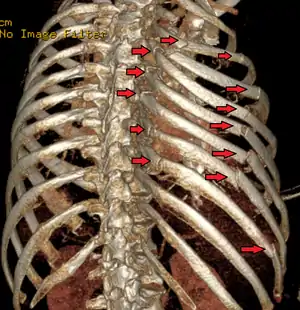

| A 3D reconstruction from a CT scan showing a flail chest. Arrows mark the rib fractures. | |

It occurs when multiple adjacent ribs are broken in multiple places, separating a segment, so a part of the chest wall moves independently. The number of ribs that must be broken varies by differing definitions: some sources say at least two adjacent ribs are broken in at least two places,[2] some require three or more ribs in two or more places.[3] The flail segment moves in the opposite direction to the rest of the chest wall: because of the ambient pressure in comparison to the pressure inside the lungs, it goes in while the rest of the chest is moving out, and vice versa. This so-called "paradoxical breathing"[4] is painful and increases the work involved in breathing.

Flail chest typically occurs when three or more adjacent ribs are fractured in two or more places, allowing that segment of the thoracic wall to displace and move independently of the rest of the chest wall. Flail chest can also occur when ribs are fractured proximally in conjunction with disarticulation of costal cartilages distally. For the condition to occur, generally there must be a significant force applied over a large surface of the thorax to create the multiple anterior and posterior rib fractures. Rollover and crushing injuries most commonly break ribs at only one point, whereas for flail chest to occur a significant impact is required, breaking the ribs in two or more places.[12] This can be caused by forceful accidents such as the aforementioned vehicle collisions or significant falls. In the elderly, it can be caused by deterioration of bone, although rare. In children, the majority of flail chest injuries result from common blunt force traumas or metabolic bone diseases, including a group of genetic disorders known as osteogenesis imperfecta.[13]